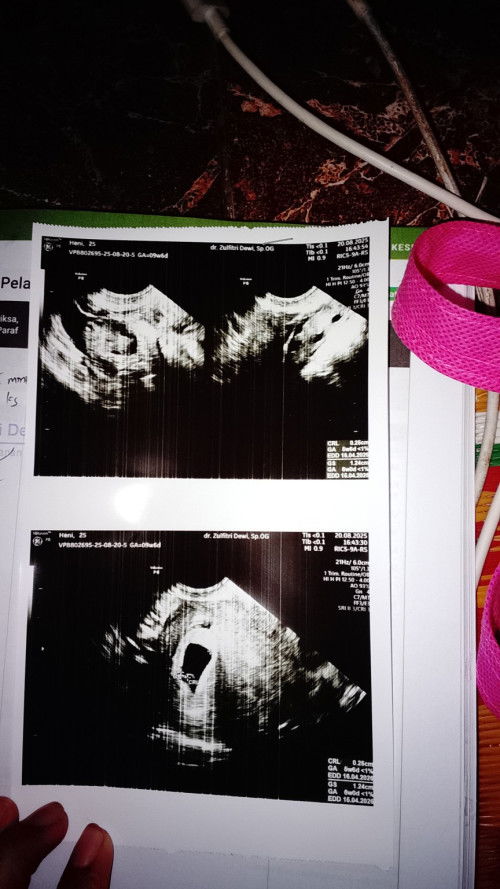

BUN Kenapa hamil 5 minggu lebih 4 hari masih mengluarkan flekk ,wajar gak bun? mintaa saran

risiko bun kalo keluar flek.. diperiksakan bun